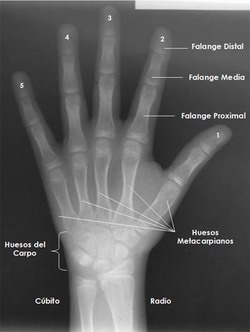

Los patrones de osificación se dan de manera ideal a nivel de las manos, ya que de los treinta huesos que componen cada miembro superior, veintinueve están involucrados en su radiografía: diáfisis, epífisis y extremo distal de cúbito y radio, ocho carpianos, cinco metacarpianos y catorce falanges. (3)

Imagen 1. Huesos del Carpo

Fuente: Elaboración Propia

Los dedos se denominan con las cifras 1 a 5 a partir del pulgar. (5)

Imagen 2. Huesos de la Mano y Numeración de los Dedos

Nomenclatura

1. Diáfisis de la falange distal del pulgar. (DP1).

2. Diáfisis de la falange proximal del pulgar. (PP1).

3. Hueso sesamoideo en la articulación metacarpofalángica del pulgar. (S).

4. Diáfisis de la falange distal del dedo índice. (DP2).

5. Diáfisis de la segunda falange del dedo índice. (MP2).

6. Diáfisis de la falange proximal del dedo índice. (PP2).

7. Diáfisis de la falange distal del dedo medio. (DP3).

8. Diáfisis de la segunda falange del dedo medio. (MP3).

9. Diáfisis de la falange proximal del dedo medio. (PP3).

10. Diáfisis de la falange distal del dedo anular. (DP4).

11. Diáfisis de la segunda falange del dedo anular. (MP4).

12. Diáfisis de la falange proximal del dedo anular. (PP4).

13. Diáfisis de la falange distal del dedo meñique. (DP5).

14. Diáfisis de la segunda falange del dedo meñique. (MP5).

15. Diáfisis de la falange proximal del dedo meñique. (PP5).

16. Diáfisis del primer hueso metacarpiano.

17. Diáfisis del segundo hueso meta-carpiano.

18. Diáfisis del tercer hueso metacarpiano.

19. Diáfisis del cuarto hueso metacarpiano.

20. Diáfisis del quinto hueso metacarpiano.

21. Trapecio.

22. Trapezoide.

23. Hueso grande.

24. Ganchoso.

25. Apófisis uniforme del ganchoso. (H).

26. Piramidal.

27. Pisiforme. (Pisi).

28. Semilunar.

29. Escafoides.

30. Diáfisis distal del Radio. (R).

31. Diáfisis distal del cúbito.